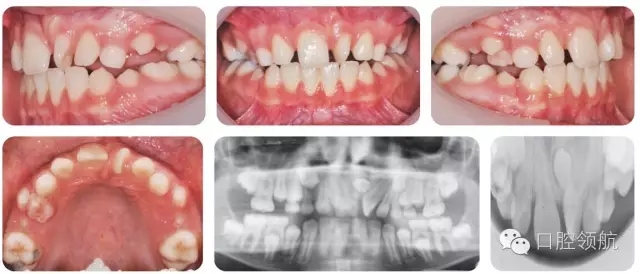

10歲的男性患者,由全科牙醫(yī)轉(zhuǎn)診。該患者健康情況良好,主訴是上前牙不美觀(圖2.16)。

圖2.16

● 混合牙列,III類切牙關(guān)系,前牙覆減小但未出現(xiàn)開牙合。

● 雙側(cè)磨牙1/2牙尖II類關(guān)系。

● 上中線左偏。

● UL1近中腭側(cè)旋轉(zhuǎn)。

上頜中線處存在未萌出的多生牙。

上頜中線處多生牙。形態(tài)為錐形,倒置??赡苁钦卸嗌?。

外科拔除多生牙。固定矯治器糾正UL1扭轉(zhuǎn)??紤]拔除兩顆上頜前磨牙以解除擁擠,排齊牙列。去除矯治器后上頜采用舌側(cè)絲粘結(jié)式保持器,以免扭轉(zhuǎn)復(fù)發(fā)。